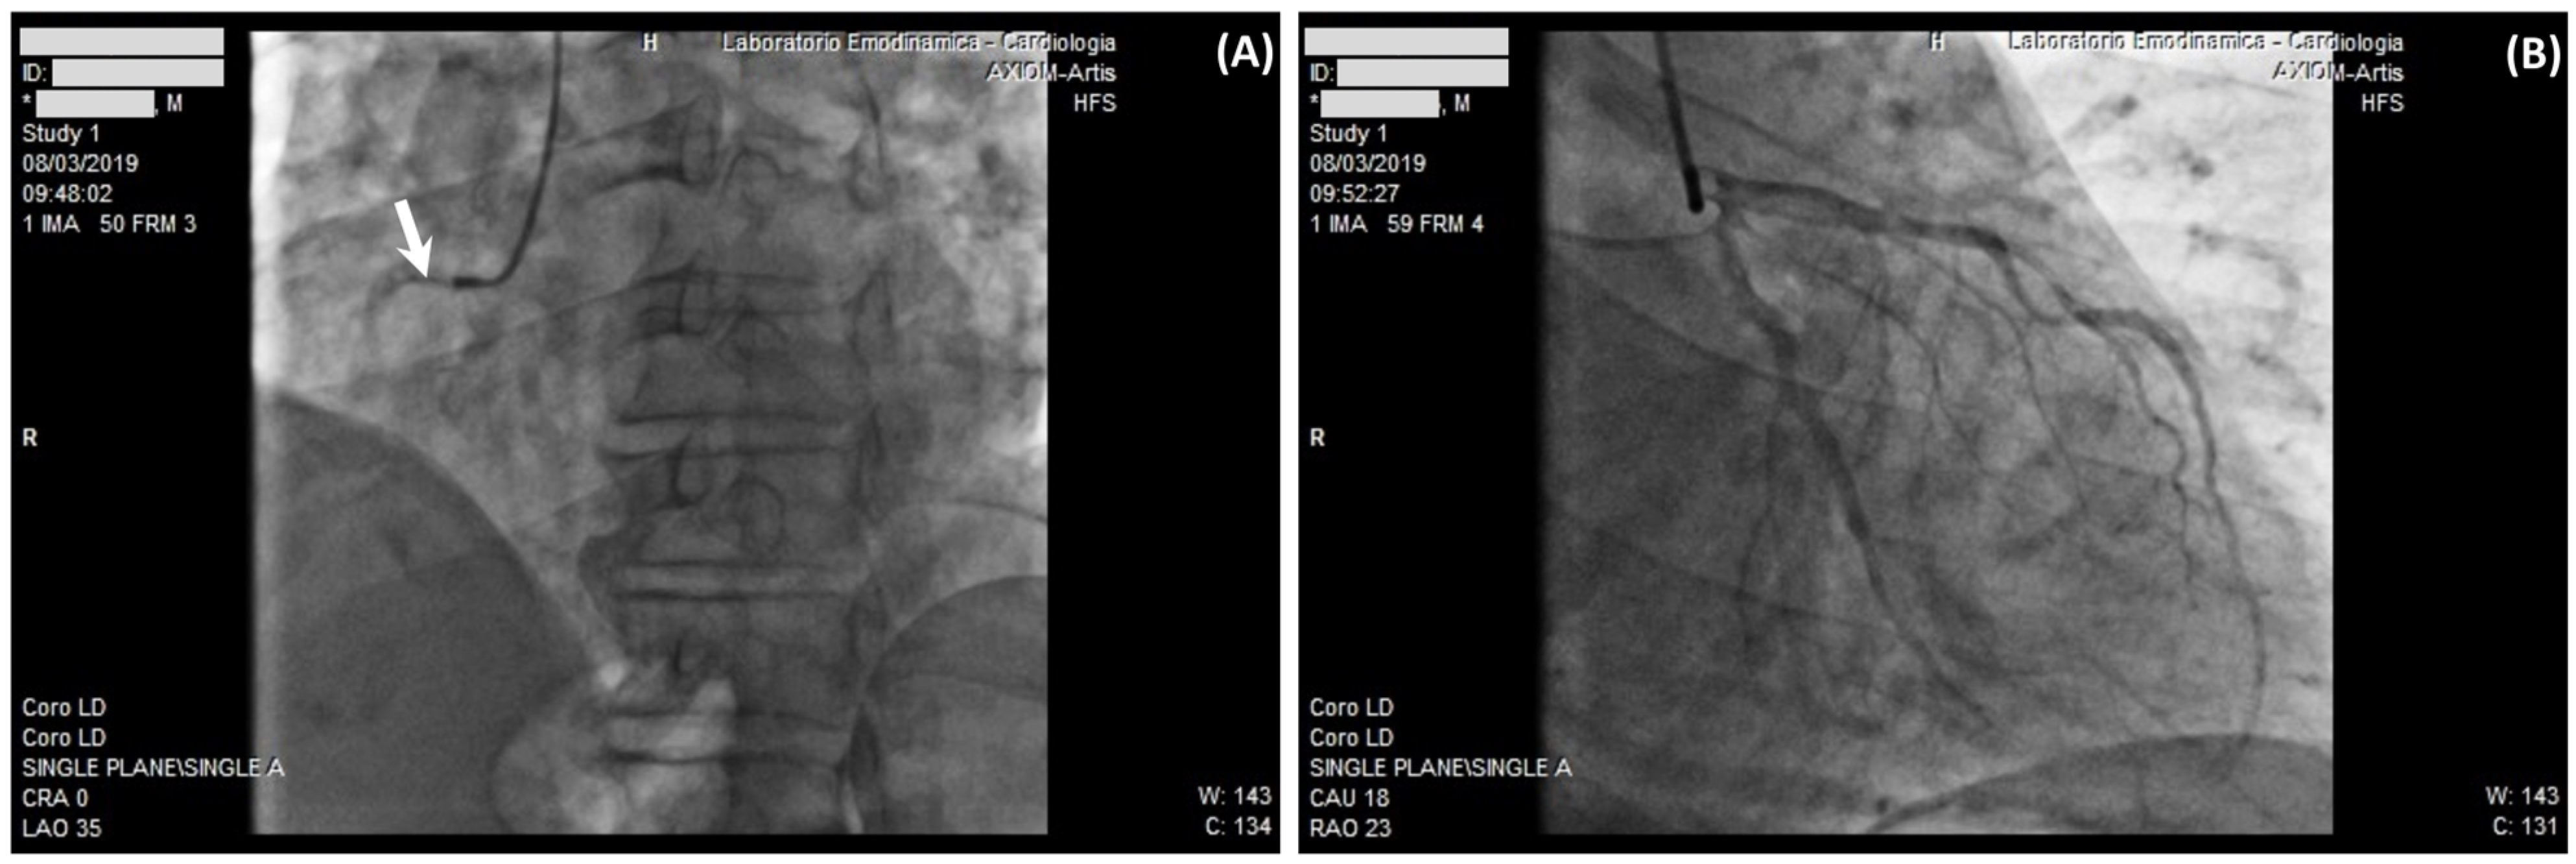

2.2. Case 2